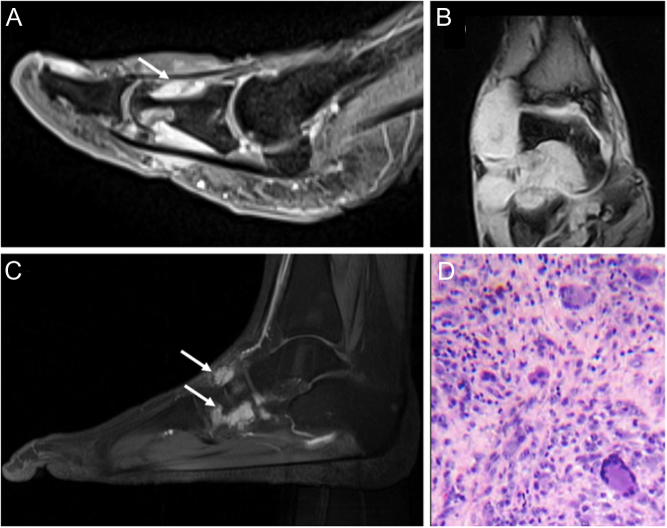

Tumors of the foot are a heterogeneous group of neoplasms that either affect soft tissues or bone, with a predominance being benign. Mistakes in the diagnosis of neoplastic conditions are common. A correct diagnostic approach supported by radiological and histological examination is mandatory. In this review, we highlight current standards in diagnosis, clinicopathological presentation, and imaging features.